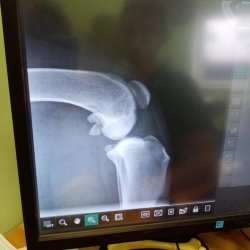

Mia s utrženými předními křížovými vazy

Mia je třicetisedmi kilogramová kříženka rotvajlera přijatá do Dočasek DeDe. Mia podstoupila kastraci a ve spojitosti s jejím horším sedáním a vstáváním bylo panem veterinářem provedeno vyšetření a byla diagnostikována dysplazie kyčelních kloubů, ale bohužel také utržení obou předních křížových vazů. Jistě tím Mia trpí již dlouho, s chůzí nemá žádný problém, nicméně kolénka má oteklá. A tak musí tato rotvajleří slečna zhubnout a podstoupit operaci křížových vazů na obou nohách. Mia shání novou dočasnou péči i případnou adopci.